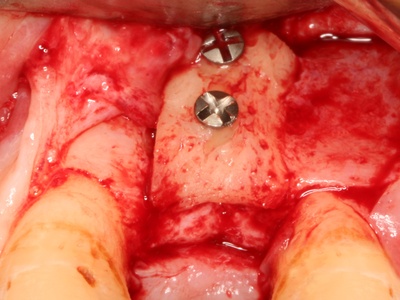

| Dental Implant Surgery | Oral Surgery/Implantology | Replace tooth | Open/Minimally invasive |

Dental Implant Surgery

Surgical placement of a titanium post into the jawbone to support a replacement tooth or bridge.